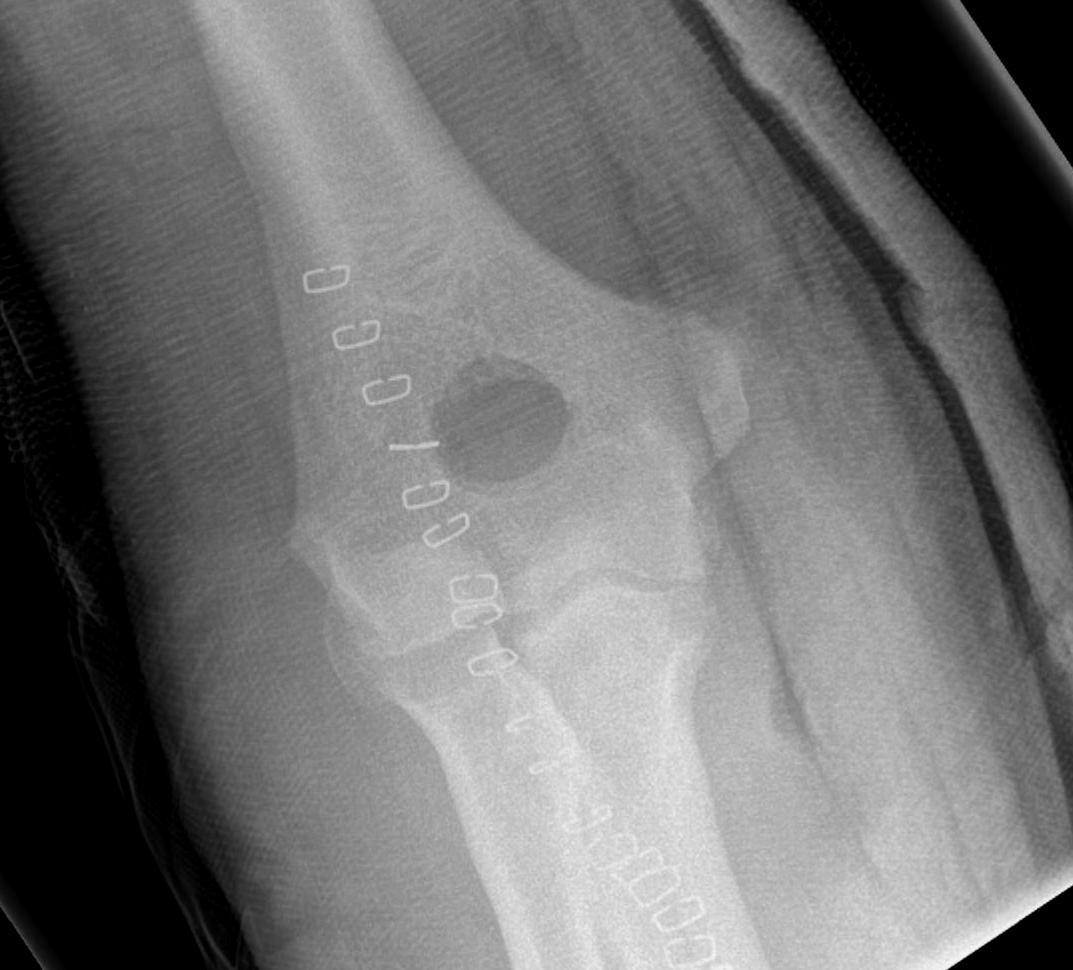

CT

Define olecranon and coranoid process osteophytes

Identification loose bodies

Osteophyte of the olecranon likely impinging in extension

CT demonstrating loose bodies in the ulnohumeral joint

Multiple loose bodies in anterior and posterior elbow joint